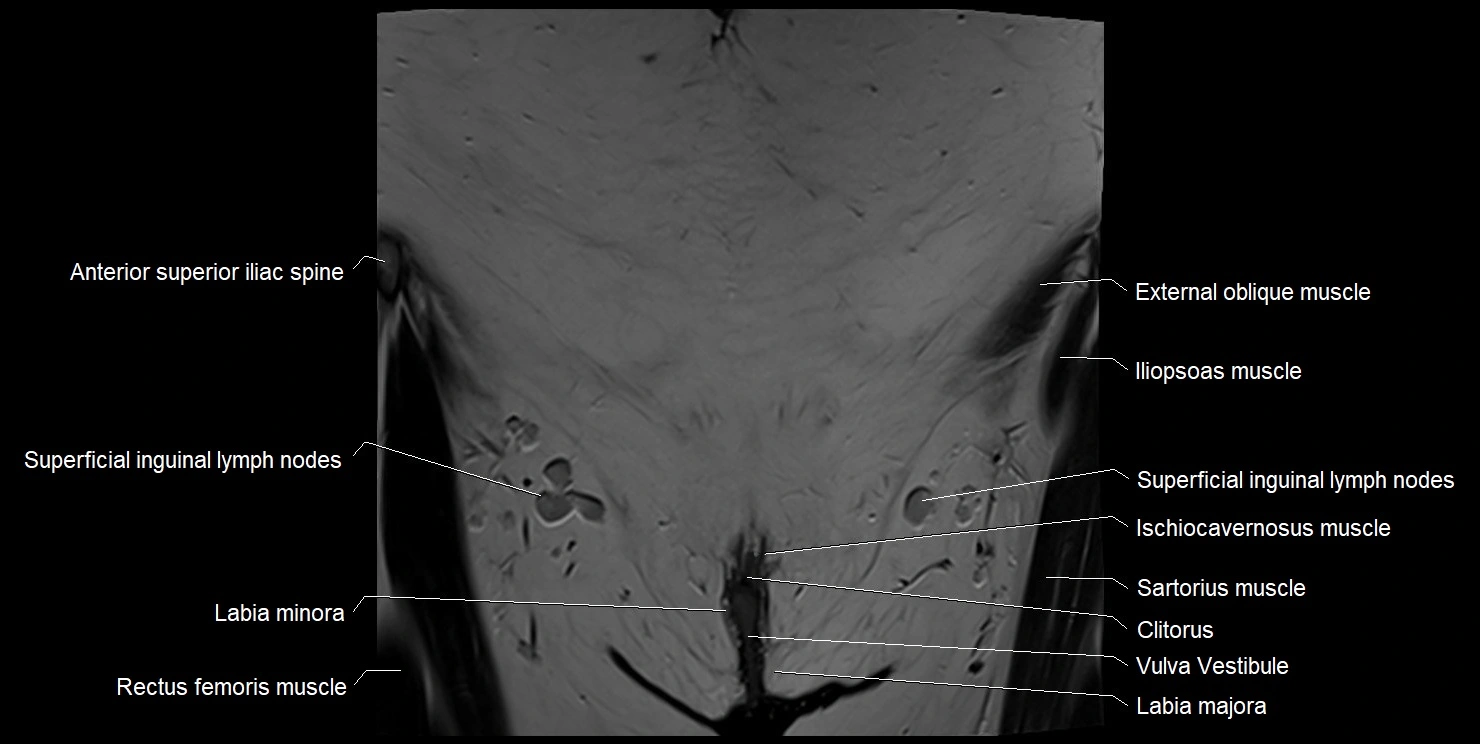

- Anterior superior iliac spine

- Clitoris

- Gracilis muscle

- Ischiocavernosus muscle (Female)

- Labia majora

- Labia minora

- Mons pubis

- Sartorius muscle

- Superficial inguinal lymph nodes